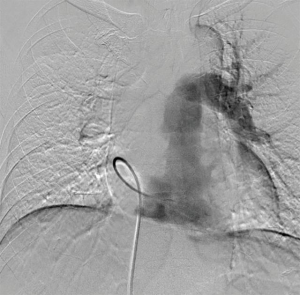

A 58-year-old man was referred to our hospital with a fever and dyspnea on exertion. Enhanced computed tomography showed low-attenuation filling defects occupying the entire luminal diameter of the right main PA, peripherally extending into the right interlobar PA (Figure 1). Positron emission tomography demonstrated an intense uptake of florine-18 fluorodeoxyglucose in the intraluminal defects, with a maximum standardized uptake value of 15.2 (Figure 2). A pulmonary angiogram showed severe stenosis of the right main PA (Figure 3). Right heart catheterization revealed a severely elevated systolic right ventricular pressure of 76 mmHg. Pulmonary function tests showed a mild restrictive ventilatory disorder with vital capacity of 3.05 L (79.6% of predicted value) and forced expiratory volume in 1 second of 2.20 L (70.1% of predicted value). The patient’s condition rapidly deteriorated and he became bed-bound. Based on these findings, PA sarcoma was clinically suspected, and the initial surgical strategy consisted of pulmonary endarterectomy and right pneumonectomy, followed by reimplantation of the right lower lobe in order to preserve the post-operative pulmonary function. All procedures performed in this study were in accordance with the Helsinki Declaration (as revised in 2013). Informed consent was obtained from the patient for publication of this manuscript and any accompanying images.